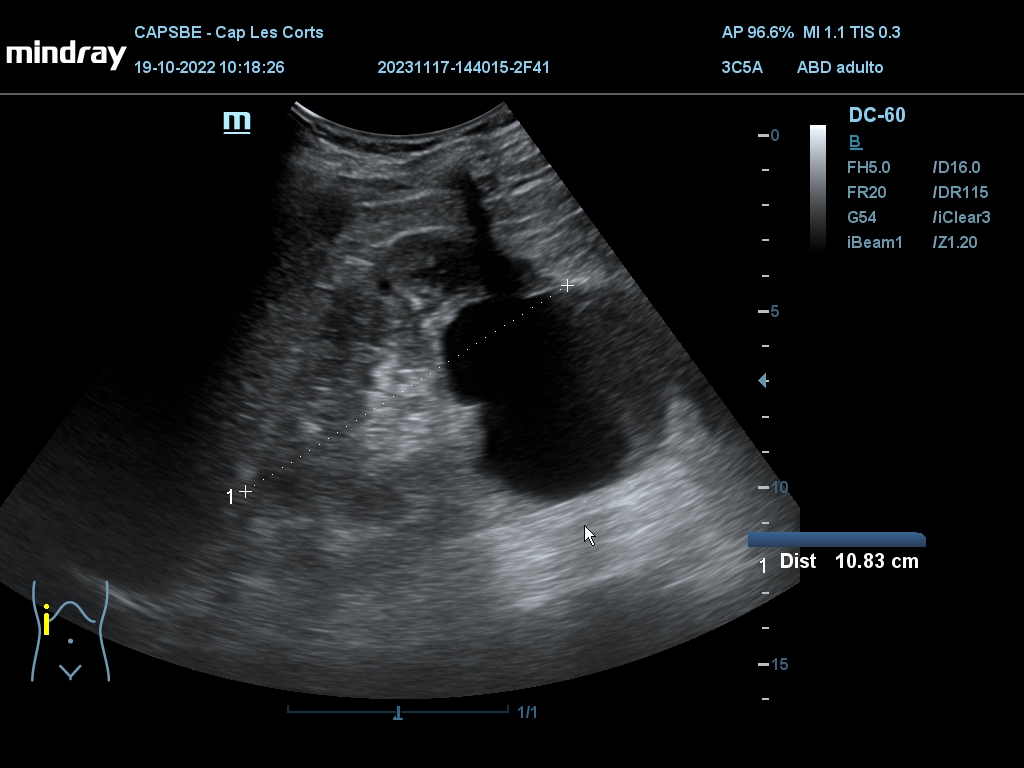

Hallazgos ecográficos

Derrame pericárdico. Vesícula biliar con grosor parietal de 1,6 cm, heterogénea, no se moviliza con cambios posturales. Quistes renales derechos, mayor de 7 cm. Aorta ateromatosa y aneurismática de 36 x 42 mm. Sin líquido intraabdominal.

(Se adjuntan imágenes del derrame, engrosamiento biliar, riñón derecho y aneurisma de aorta).

En este caso observamos como la ecografía en Atención Primaria (con exploración más global) permite encontrar diferentes hallazgos incidentales, algunos significativos (cardiopatía) y otros que requieren estudio y seguimiento, adelantando mucho el proceso de diagnóstico y detectando a tiempo situaciones que pueden ser urgentes, en especial el aneurisma de aorta.